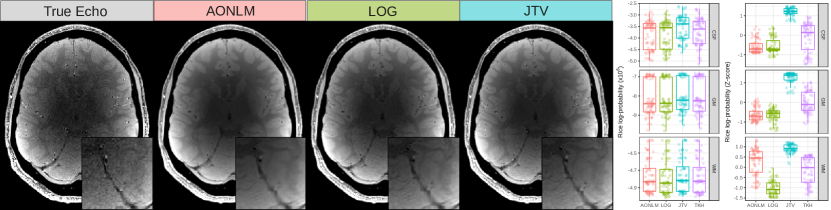

Leave-One-Echo-Out. The distribution of Rice loglikelihoods and Z-scores for each methods are depicted in Fig. 1 in the form of Tukey’s boxplots. In the parenchyma, JTV obtained the best score (mean log-likelihood: -9.15×1069.15superscript1069.15\times 10^{6}, mean Z-score: 1.191.191.19) followed by TKH (-9.26×1069.26superscript1069.26\times 10^{6} and -0.050.050.05), AONLM (-9.34×1069.34superscript1069.34\times 10^{6} and -0.410.410.41) and LOG (-9.35×1069.35superscript1069.35\times 10^{6} and -0.720.720.72). As some echoes are harder to predict than others (typically, early echoes because their absence impacts the estimator of the intercept the most) the log-pdf has quite a high variance. However, Z-scores show that, for each echo, JTV does consistently better than all other methods. As can be seen in Fig. 1, JTV is particularly good at preserving vessels.

Figure 1: Leave-one-echo out prediction. Left: the true PDw echo at TE=9.7subscript𝑇𝐸9.7T_{E}=9.7ms from the 5th repeat and three predicted images. Right: boxplots of the Rice log-pdf and corresponding Z-score computed for each method within GM, WM and CSF masks.